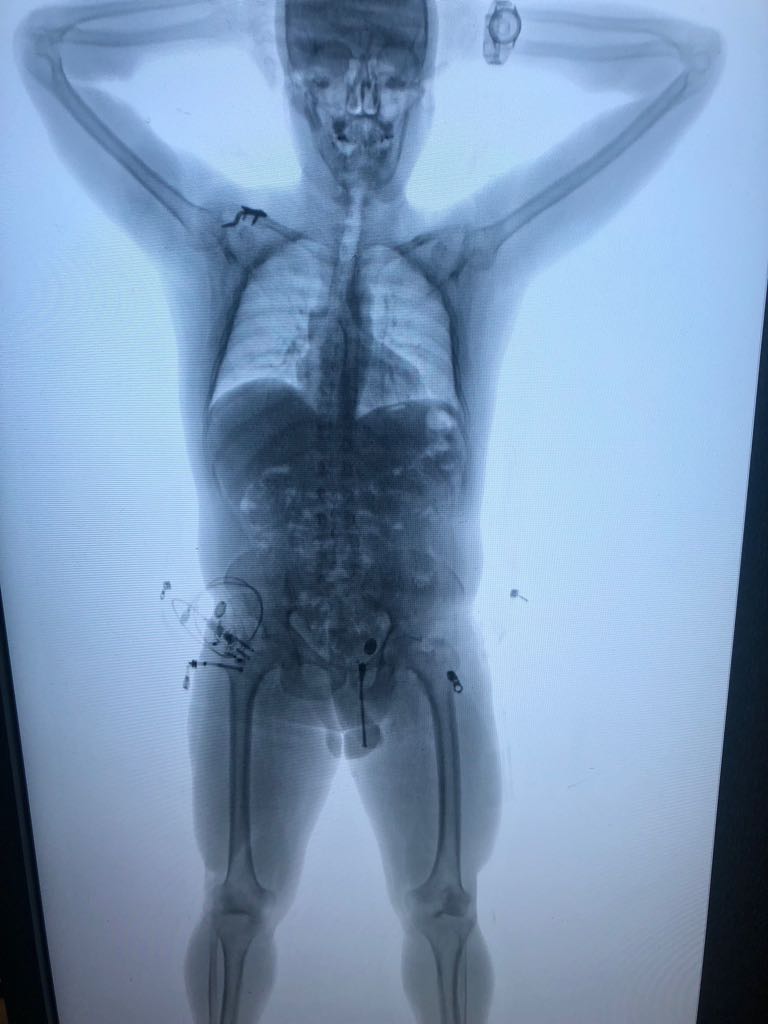

El cuarto capturado fue abordado por unidades de la Dirección de Antinarcóticos en el momento que esperaba ingresar a migración, a esta persona se le noto algo nervioso cuando le hicieron la perfilación lo que generó dudas entre los uniformados y al conducirlo al bodyscan confeso que había ingerido 89 cápsulas de cocaína por lo que fue necesario su traslado al centro asistencial más cercano. El capturado pretendía llegar al aeropuerto de Barajas en España.